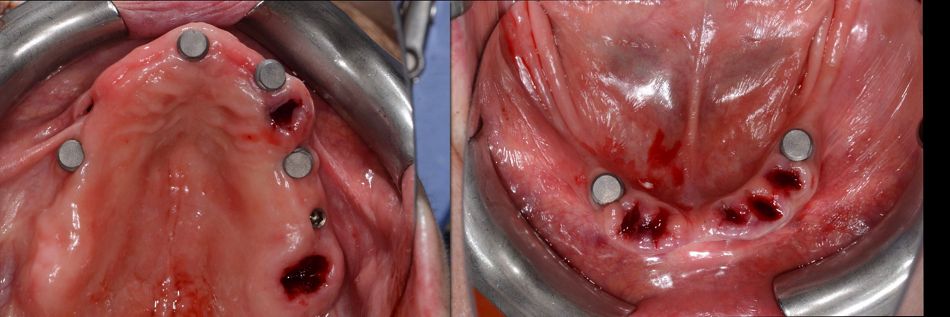

The lower jaw was then treated under local anesthesia. Prior to the surgical phase, the prosthesis was removed, followed by the extraction of teeth #34 and #43 (Figs. 43,44).

For the lower jaw, implants were placed using a surgical guide following the planned drilling protocol (Figs. 45,46).

Implant placement was performed using Straumann® BLC™ implants: a Ø 3.3 mm Regular Base, 12 mm SLActive® implant at site 34 and a Ø 3.3 mm Regular Base, 10 mm SLActive® implant at site 43 (Fig. 47).

Fig. 47

Dental bone grafting material was used for GBR in the post-extractive implant sites 34 and 43.

Healing abutments were placed, and primary stability of the implants was confirmed. Postoperative evaluation after immediate flapless implant placement showed stable soft tissues at the surgical sites, with minimal trauma observed (Fig. 48).